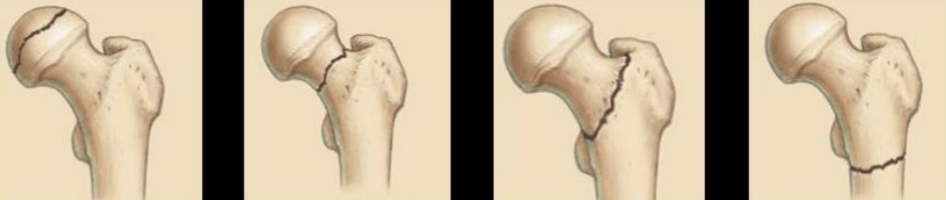

13

Q

A

Cabeza

Cuello

Intertrocantereo

Subtrocantereas

14

Fx cuello femoral

15

Fx intertrocanterica

16